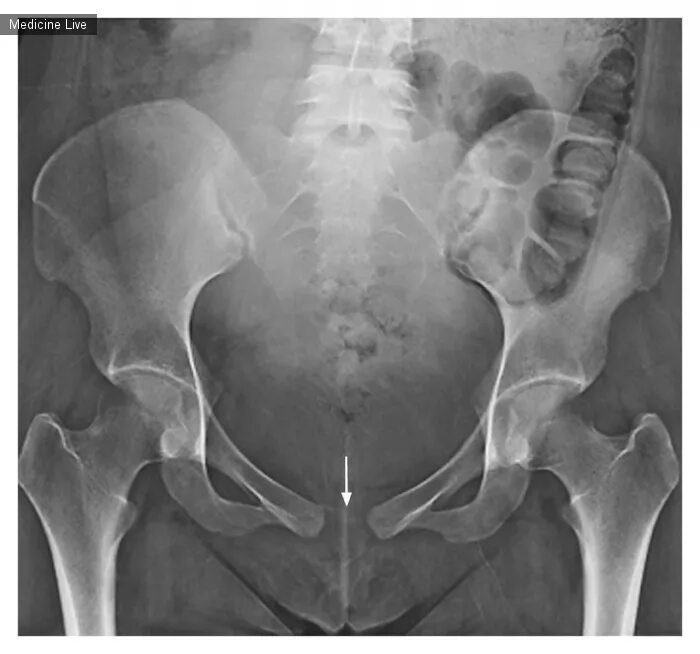

Боли в симфизе